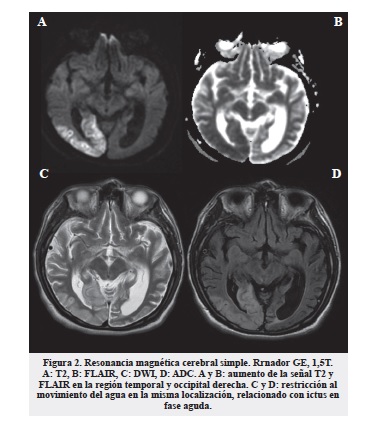

En la TAC cerebral simple como principal hallazgo encontramos una hipodensidad cortico - subcortical parietal inferior y occipital derecha, relacionada con infarto en fase aguda de evolución en territorio de arteria cerebral posterior derecha. Al igual que aumento compensatorio del volumen de los espacios subaracnoideos supratentoriales por cambios de atrofia cortical y ventriculomegalia compensatoria a la pérdida de volumen parenquimatoso (figura 1).

En la resonancia magnética cerebral simple se encontró disminución de la señal T1 en la corteza occipital y occipitotemporal derecha y aumento de la señal T2, FLAIR y restricción al movimiento del agua en difusión de las localizaciones afectadas lo cual se encuentra en relación con ictus en fase aguda (figura 2). Evidenciamos además atrofia cortical supra e infratentorial, de predominio biparietal y bioccipital, prominente para la edad. No encontramos calcificaciones ganglios basales en los estudios realizados.